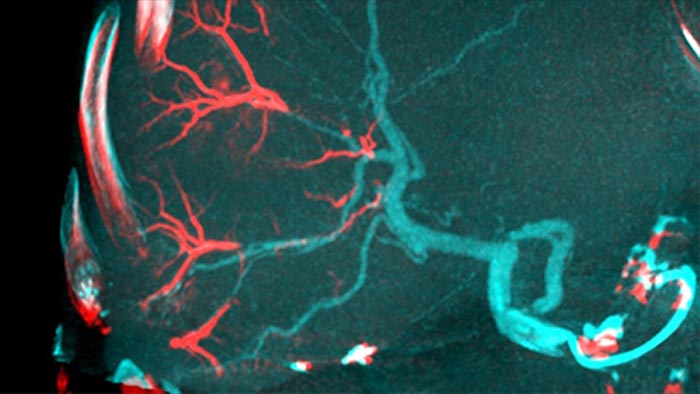

Al abrir el arco a la izquierda del paciente, CBCT Open permite la colocación descentrada de la mesa del paciente y, por lo tanto, mejor centrado del campo de visión3-4. Aumenta significativamente la cobertura de la imagen para ayudar a visualizar tumores en la periferia del hígado4.